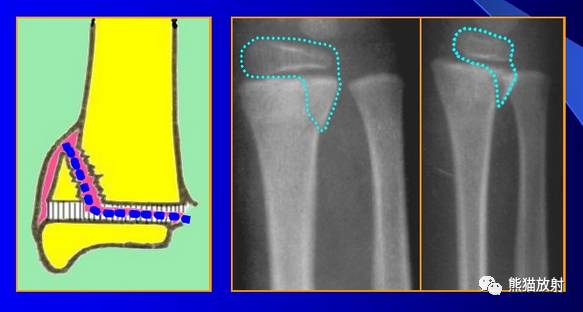

Salter-Harris III型:骨折累及骺板及骨骺,属于关节内骨折,可导致生长停滞。

第三型(Ⅲ型) 骨骺骨折。属于关节内骨折,骨折线从关节面开始穿过骨骺,再平行横越部分骺板的肥大层。该型占骨骺损伤的4%。多发生在胫骨远端内侧或外侧和肱骨远端外侧。无移位关节面平整者预后良好,有移位者需切开复位内固定,—般移位超过2mm者既是切开复位内固定的适应证。